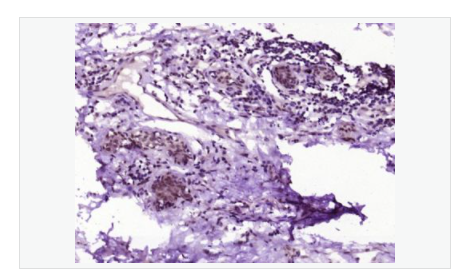

| 產(chǎn)品應(yīng)用 | WB=1:500-2000 ELISA=1:5000-10000 IHC-P=1:100-500 IHC-F=1:100-500 IF=1:100-500 (石蠟切片需做抗原修復(fù)) not yet tested in other applications. optimal dilutions/concentrations should be determined by the end user. |

| 產(chǎn)品介紹 | Acts as a growth inhibitor. Can activate TP53/p53, causes G1 arrest and collaborates with CDKN2A to restrict proliferation, but does not require either protein to inhibit DNA synthesis. Redistributes CDKN2A into the nucleoplasm. Involved in maintaining chromosomal stability. There are two isoforms. Function: Acts as a growth inhibitor. Can activate p53/TP53, causes G1 arrest and collaborates with CDKN2A to restrict proliferation, but does not require either protein to inhibit DNA synthesis. Redistributes CDKN2A into the nucleoplasm. Involved in maintaining chromosomal stability. Subunit: Interacts with CDKN2A and MDM2. Subcellular Location: Nucleus. Tissue Specificity: Widely expressed at low levels in most tissues, with highest levels in pancreas, lung and liver. Expression is decreased in primary tumors including lung, liver, breast, pancreas and kidney carcinomas, chronic lymphocytic leukemia and diffuse large B-cell lymphoma. Post-translational modifications: Ubiquitinated; mediated by MDM2 and leading to its subsequent proteasomal degradation. Similarity: Belongs to the TBRG1 family. Contains 1 FYR C-terminal domain. Contains 1 FYR N-terminal domain. SWISS: Q3YBR2 Gene ID: 84897 Database links: Entrez Gene: 84897 Human Entrez Gene: 21376 Mouse Omim: 610614 Human SwissProt: Q3YBR2 Human SwissProt: Q3UB74 Mouse Unigene: 436410 Human Unigene: 28689 Mouse Unigene: 129282 Rat Important Note: This product as supplied is intended for research use only, not for use in human, therapeutic or diagnostic applications. |